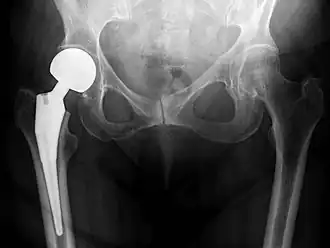

Metal on metal prosthetic hip

Cement-free implant sixteen days after surgery. Femoral component is cobalt chromium combined with titanium which induces bone growth into the implant. Ceramic head. Acetabular cup coated with bone growth-inducing material and held temporarily in place with a single screw.